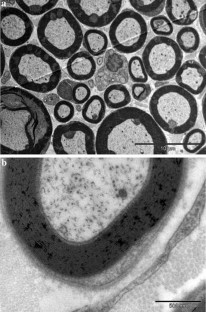

The purpose of the current study was to establish a valid protocol for nerve cryopreservation, and to evaluate if the addition of albumin supposed any advantage in the procedure. We compared a traditional cryopreservation method that uses dimethyl sulfoxide (DMSO) as cryoprotectant, to an alternative method that uses DMSO and albumin. Six Wistar Lewis rats were used to obtain twelve 20 mm fragments of sciatic nerve. In the first group, six fragments were cryopreserved in 199 media with 10% DMSO, with a temperature decreasing rate of 1 °C per minute. In the second group, six fragments were cryopreserved adding 4% human albumin. The unfreezing process consisted of sequential washings with saline in the first group, and saline and 20% albumin in the second group at 37 °C until the crioprotectant was removed. Structural evaluation was performed through histological analysis and electronic microscopy. The viability was assessed with the calcein-AM (CAM) and 4′,6-diamino-2-fenilindol (DAPI) staining. Histological results showed a correct preservation of peripheral nerve architecture and no significant differences were found between the two groups. However, Schwann cells viability showed in the CAM-DAPI staining was significantly superior in the albumin group. The viability of Schwann cells was significantly increased when albumin was added to the nerve cryopreservation protocol. However, no significant structural differences were found between groups. Further studies need to be performed to assess the cryopreserved nerve functionality using this new method.